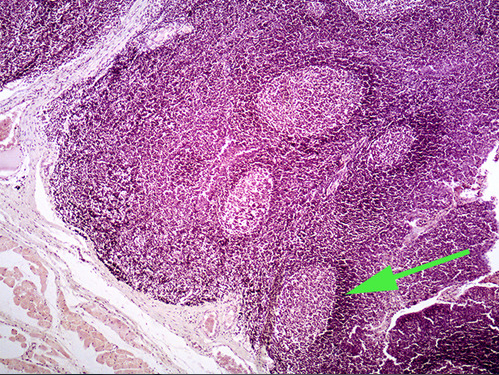

The small structure marked by a green arrow is a lymph NODE

The area of the lymph node indicated by the green arrow is the medulla